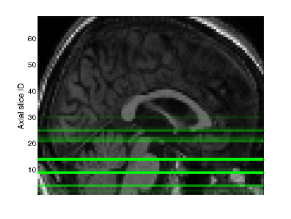

In summary, we consider a global view of data and a single GP which is specified with multiple covariance functions and aimed at single task learning. Despite the global view, the subtlety of MKL-AsRD should be noted. We wish to exploit the locality information in order to better capture the spatial patterns of brain atrophy. In this regard, we consider the portions of high-dimensional inputs, instead of the clusters obtained by an analysis of the joint feature space (Figure 1).

X= x1,1 x1,2 x1,3 x1,d x1,D xk,1 xk,2 xk,3 xk,d xk,D xN,1 xN,2 xN,3 xN,d xN,D []local viewglobal viewsubspace𝑋 subscript𝑥11 subscript𝑥12 subscript𝑥13 subscript𝑥1𝑑 subscript𝑥1𝐷 subscript𝑥𝑘1 subscript𝑥𝑘2 subscript𝑥𝑘3 subscript𝑥𝑘𝑑 subscript𝑥𝑘𝐷 subscript𝑥𝑁1 subscript𝑥𝑁2 subscript𝑥𝑁3 subscript𝑥𝑁𝑑 subscript𝑥𝑁𝐷 fragments[fragments]local viewglobal viewsubspaceX=\leavevmode\hbox to315.95pt{\vbox to131.21pt{\pgfpicture\makeatletter\hbox{\hskip 179.73059pt\lower-66.34442pt\hbox to0.0pt{\pgfsys@beginscope\pgfsys@invoke{ }\definecolor{pgfstrokecolor}{rgb}{0,0,0}\pgfsys@color@rgb@stroke{0}{0}{0}\pgfsys@invoke{ }\pgfsys@color@rgb@fill{0}{0}{0}\pgfsys@invoke{ }\pgfsys@setlinewidth{0.4pt}\pgfsys@invoke{ }\nullfont\hbox to0.0pt{\pgfsys@beginscope\pgfsys@invoke{ } {}{}{}{{}}{{}}{{}}{ {}}{{}}\hbox{\hbox{\hbox{\hbox{{\pgfsys@beginscope\pgfsys@invoke{ }{\offinterlineskip{}{}{{{}}{{}}{{}}{{}}{{}}{{}}{{}}{{}}{{}}{{}}{{}}{{}}{{}}{{}}{{}}{{}}{{}}{{}}{{}}{{}}{{}}{{}}{{}}{{}}{{}}{{}}{{}}{{}}{{}}{{}}{{}}{{}}{{}}{{}}{{}}}{{{}}}{{}{}{{ {}{}}}{ {}{}} {{}{{}}}{{}{}}{}{{}{}} { }{{{{}}\pgfsys@beginscope\pgfsys@invoke{ }\pgfsys@transformcm{1.0}{0.0}{0.0}{1.0}{-127.13118pt}{-57.0295pt}\pgfsys@invoke{ }\hbox{\vbox{\halign{\pgf@matrix@init@row\pgf@matrix@step@column{\pgf@matrix@startcell#\pgf@matrix@endcell}&#\pgf@matrix@padding&&\pgf@matrix@step@column{\pgf@matrix@startcell#\pgf@matrix@endcell}&#\pgf@matrix@padding\cr\hfil\hskip 18.33302pt\hbox{{\pgfsys@beginscope\pgfsys@invoke{ }{{}}\hbox{\hbox{{\pgfsys@beginscope\pgfsys@invoke{ }{{}{}{{ {}{}}}{ {}{}} {{}{{}}}{{}{}}{}{{}{}} { }{{{{}}\pgfsys@beginscope\pgfsys@invoke{ }\pgfsys@transformcm{1.0}{0.0}{0.0}{1.0}{-15.00002pt}{0.0pt}\pgfsys@invoke{ }\hbox{{\definecolor{pgfstrokecolor}{rgb}{0,0,0}\pgfsys@color@rgb@stroke{0}{0}{0}\pgfsys@invoke{ }\pgfsys@color@rgb@fill{0}{0}{0}\pgfsys@invoke{ }\hbox{\minipage[t]{30.00005pt}\leavevmode\hbox{}${x_{1,1}}$\endminipage} }}\pgfsys@invoke{\lxSVG@closescope }\pgfsys@endscope}}} \pgfsys@invoke{\lxSVG@closescope }\pgfsys@endscope}}} \pgfsys@invoke{\lxSVG@closescope }\pgfsys@endscope{}}}&\hskip 18.33302pt\hfil&\hfil\hskip 17.93303pt\hbox{{\pgfsys@beginscope\pgfsys@invoke{ }{{}}\hbox{\hbox{{\pgfsys@beginscope\pgfsys@invoke{ }{{}{}{{ {}{}}}{ {}{}} {{}{{}}}{{}{}}{}{{}{}} { }{{{{}}\pgfsys@beginscope\pgfsys@invoke{ }\pgfsys@transformcm{1.0}{0.0}{0.0}{1.0}{-15.00002pt}{0.0pt}\pgfsys@invoke{ }\hbox{{\definecolor{pgfstrokecolor}{rgb}{0,0,0}\pgfsys@color@rgb@stroke{0}{0}{0}\pgfsys@invoke{ }\pgfsys@color@rgb@fill{0}{0}{0}\pgfsys@invoke{ }\hbox{\minipage[t]{30.00005pt}\leavevmode\hbox{}${x_{1,2}}$\endminipage} }}\pgfsys@invoke{\lxSVG@closescope }\pgfsys@endscope}}} \pgfsys@invoke{\lxSVG@closescope }\pgfsys@endscope}}} \pgfsys@invoke{\lxSVG@closescope }\pgfsys@endscope{}}}&\hskip 18.33302pt\hfil&\hfil\hskip 17.93303pt\hbox{{\pgfsys@beginscope\pgfsys@invoke{ }{{}}\hbox{\hbox{{\pgfsys@beginscope\pgfsys@invoke{ }{{}{}{{ {}{}}}{ {}{}} {{}{{}}}{{}{}}{}{{}{}} { }{{{{}}\pgfsys@beginscope\pgfsys@invoke{ }\pgfsys@transformcm{1.0}{0.0}{0.0}{1.0}{-15.00002pt}{0.0pt}\pgfsys@invoke{ }\hbox{{\definecolor{pgfstrokecolor}{rgb}{0,0,0}\pgfsys@color@rgb@stroke{0}{0}{0}\pgfsys@invoke{ }\pgfsys@color@rgb@fill{0}{0}{0}\pgfsys@invoke{ }\hbox{\minipage[t]{30.00005pt}\leavevmode\hbox{}${x_{1,3}}$\endminipage} }}\pgfsys@invoke{\lxSVG@closescope }\pgfsys@endscope}}} \pgfsys@invoke{\lxSVG@closescope }\pgfsys@endscope}}} \pgfsys@invoke{\lxSVG@closescope }\pgfsys@endscope{}}}&\hskip 18.33302pt\hfil&\hfil\hskip 17.93303pt\hbox{{\pgfsys@beginscope\pgfsys@invoke{ }{{}}\hbox{\hbox{{\pgfsys@beginscope\pgfsys@invoke{ }{{}{}{{ {}{}}}{ {}{}} {{}{{}}}{{}{}}{}{{}{}} { }{{{{}}\pgfsys@beginscope\pgfsys@invoke{ }\pgfsys@transformcm{1.0}{0.0}{0.0}{1.0}{-15.00002pt}{0.0pt}\pgfsys@invoke{ }\hbox{{\definecolor{pgfstrokecolor}{rgb}{0,0,0}\pgfsys@color@rgb@stroke{0}{0}{0}\pgfsys@invoke{ }\pgfsys@color@rgb@fill{0}{0}{0}\pgfsys@invoke{ }\hbox{\minipage[t]{30.00005pt}\leavevmode\hbox{}${\cdots}$\endminipage} }}\pgfsys@invoke{\lxSVG@closescope }\pgfsys@endscope}}} \pgfsys@invoke{\lxSVG@closescope }\pgfsys@endscope}}} \pgfsys@invoke{\lxSVG@closescope }\pgfsys@endscope{}}}&\hskip 18.33302pt\hfil&\hfil\hskip 17.93303pt\hbox{{\pgfsys@beginscope\pgfsys@invoke{ }{{}}\hbox{\hbox{{\pgfsys@beginscope\pgfsys@invoke{ }{{}{}{{ {}{}}}{ {}{}} {{}{{}}}{{}{}}{}{{}{}} { }{{{{}}\pgfsys@beginscope\pgfsys@invoke{ }\pgfsys@transformcm{1.0}{0.0}{0.0}{1.0}{-15.00002pt}{0.0pt}\pgfsys@invoke{ }\hbox{{\definecolor{pgfstrokecolor}{rgb}{0,0,0}\pgfsys@color@rgb@stroke{0}{0}{0}\pgfsys@invoke{ }\pgfsys@color@rgb@fill{0}{0}{0}\pgfsys@invoke{ }\hbox{\minipage[t]{30.00005pt}\leavevmode\hbox{}${x_{1,d}}$\endminipage} }}\pgfsys@invoke{\lxSVG@closescope }\pgfsys@endscope}}} \pgfsys@invoke{\lxSVG@closescope }\pgfsys@endscope}}} \pgfsys@invoke{\lxSVG@closescope }\pgfsys@endscope{}}}&\hskip 18.33302pt\hfil&\hfil\hskip 17.93303pt\hbox{{\pgfsys@beginscope\pgfsys@invoke{ }{{}}\hbox{\hbox{{\pgfsys@beginscope\pgfsys@invoke{ }{{}{}{{ {}{}}}{ {}{}} {{}{{}}}{{}{}}{}{{}{}} { }{{{{}}\pgfsys@beginscope\pgfsys@invoke{ }\pgfsys@transformcm{1.0}{0.0}{0.0}{1.0}{-15.00002pt}{0.0pt}\pgfsys@invoke{ }\hbox{{\definecolor{pgfstrokecolor}{rgb}{0,0,0}\pgfsys@color@rgb@stroke{0}{0}{0}\pgfsys@invoke{ }\pgfsys@color@rgb@fill{0}{0}{0}\pgfsys@invoke{ }\hbox{\minipage[t]{30.00005pt}\leavevmode\hbox{}${\cdots}$\endminipage} }}\pgfsys@invoke{\lxSVG@closescope }\pgfsys@endscope}}} \pgfsys@invoke{\lxSVG@closescope }\pgfsys@endscope}}} \pgfsys@invoke{\lxSVG@closescope }\pgfsys@endscope{}}}&\hskip 18.33302pt\hfil&\hfil\hskip 17.93303pt\hbox{{\pgfsys@beginscope\pgfsys@invoke{ }{{}}\hbox{\hbox{{\pgfsys@beginscope\pgfsys@invoke{ }{{}{}{{ {}{}}}{ {}{}} {{}{{}}}{{}{}}{}{{}{}} { }{{{{}}\pgfsys@beginscope\pgfsys@invoke{ }\pgfsys@transformcm{1.0}{0.0}{0.0}{1.0}{-15.00002pt}{0.0pt}\pgfsys@invoke{ }\hbox{{\definecolor{pgfstrokecolor}{rgb}{0,0,0}\pgfsys@color@rgb@stroke{0}{0}{0}\pgfsys@invoke{ }\pgfsys@color@rgb@fill{0}{0}{0}\pgfsys@invoke{ }\hbox{\minipage[t]{30.00005pt}\leavevmode\hbox{}${x_{1,D}}$\endminipage} }}\pgfsys@invoke{\lxSVG@closescope }\pgfsys@endscope}}} \pgfsys@invoke{\lxSVG@closescope }\pgfsys@endscope}}} \pgfsys@invoke{\lxSVG@closescope }\pgfsys@endscope}}&\hskip 18.33302pt\hfil\cr\vskip-0.4pt\cr\hfil\hskip 18.33302pt\hbox{{\pgfsys@beginscope\pgfsys@invoke{ }{{}}\hbox{\hbox{{\pgfsys@beginscope\pgfsys@invoke{ }{{}{}{{ {}{}}}{ {}{}} {{}{{}}}{{}{}}{}{{}{}} { }{{{{}}\pgfsys@beginscope\pgfsys@invoke{ }\pgfsys@transformcm{1.0}{0.0}{0.0}{1.0}{-15.00002pt}{0.0pt}\pgfsys@invoke{ }\hbox{{\definecolor{pgfstrokecolor}{rgb}{0,0,0}\pgfsys@color@rgb@stroke{0}{0}{0}\pgfsys@invoke{ }\pgfsys@color@rgb@fill{0}{0}{0}\pgfsys@invoke{ }\hbox{\minipage[t]{30.00005pt}\leavevmode\hbox{}${\vdots}$\endminipage} }}\pgfsys@invoke{\lxSVG@closescope }\pgfsys@endscope}}} \pgfsys@invoke{\lxSVG@closescope }\pgfsys@endscope}}} \pgfsys@invoke{\lxSVG@closescope }\pgfsys@endscope}}&\hskip 18.33302pt\hfil&\hfil\hskip 17.93303pt\hbox{{\pgfsys@beginscope\pgfsys@invoke{ }{{}}\hbox{\hbox{{\pgfsys@beginscope\pgfsys@invoke{ }{{}{}{{ {}{}}}{ {}{}} {{}{{}}}{{}{}}{}{{}{}} { }{{{{}}\pgfsys@beginscope\pgfsys@invoke{ }\pgfsys@transformcm{1.0}{0.0}{0.0}{1.0}{-15.00002pt}{0.0pt}\pgfsys@invoke{ }\hbox{{\definecolor{pgfstrokecolor}{rgb}{0,0,0}\pgfsys@color@rgb@stroke{0}{0}{0}\pgfsys@invoke{ }\pgfsys@color@rgb@fill{0}{0}{0}\pgfsys@invoke{ }\hbox{\minipage[t]{30.00005pt}\leavevmode\hbox{}${\vdots}$\endminipage} }}\pgfsys@invoke{\lxSVG@closescope }\pgfsys@endscope}}} \pgfsys@invoke{\lxSVG@closescope }\pgfsys@endscope}}} \pgfsys@invoke{\lxSVG@closescope }\pgfsys@endscope}}&\hskip 18.33302pt\hfil&\hfil\hskip 17.93303pt\hbox{{\pgfsys@beginscope\pgfsys@invoke{ }{{}}\hbox{\hbox{{\pgfsys@beginscope\pgfsys@invoke{ }{{}{}{{ {}{}}}{ {}{}} {{}{{}}}{{}{}}{}{{}{}} { }{{{{}}\pgfsys@beginscope\pgfsys@invoke{ }\pgfsys@transformcm{1.0}{0.0}{0.0}{1.0}{-15.00002pt}{0.0pt}\pgfsys@invoke{ }\hbox{{\definecolor{pgfstrokecolor}{rgb}{0,0,0}\pgfsys@color@rgb@stroke{0}{0}{0}\pgfsys@invoke{ }\pgfsys@color@rgb@fill{0}{0}{0}\pgfsys@invoke{ }\hbox{\minipage[t]{30.00005pt}\leavevmode\hbox{}${\ddots}$\endminipage} }}\pgfsys@invoke{\lxSVG@closescope }\pgfsys@endscope}}} \pgfsys@invoke{\lxSVG@closescope }\pgfsys@endscope}}} \pgfsys@invoke{\lxSVG@closescope }\pgfsys@endscope}}&\hskip 18.33302pt\hfil&\hfil\hskip 17.93303pt\hbox{{\pgfsys@beginscope\pgfsys@invoke{ }{{}}\hbox{\hbox{{\pgfsys@beginscope\pgfsys@invoke{ }{{}{}{{ {}{}}}{ {}{}} {{}{{}}}{{}{}}{}{{}{}} { }{{{{}}\pgfsys@beginscope\pgfsys@invoke{ }\pgfsys@transformcm{1.0}{0.0}{0.0}{1.0}{-15.00002pt}{0.0pt}\pgfsys@invoke{ }\hbox{{\definecolor{pgfstrokecolor}{rgb}{0,0,0}\pgfsys@color@rgb@stroke{0}{0}{0}\pgfsys@invoke{ }\pgfsys@color@rgb@fill{0}{0}{0}\pgfsys@invoke{ }\hbox{\minipage[t]{30.00005pt}\leavevmode\hbox{}${\cdots}$\endminipage} }}\pgfsys@invoke{\lxSVG@closescope }\pgfsys@endscope}}} \pgfsys@invoke{\lxSVG@closescope }\pgfsys@endscope}}} \pgfsys@invoke{\lxSVG@closescope }\pgfsys@endscope}}&\hskip 18.33302pt\hfil&\hfil\hskip 17.93303pt\hbox{{\pgfsys@beginscope\pgfsys@invoke{ }{{}}\hbox{\hbox{{\pgfsys@beginscope\pgfsys@invoke{ }{{}{}{{ {}{}}}{ {}{}} {{}{{}}}{{}{}}{}{{}{}} { }{{{{}}\pgfsys@beginscope\pgfsys@invoke{ }\pgfsys@transformcm{1.0}{0.0}{0.0}{1.0}{-15.00002pt}{0.0pt}\pgfsys@invoke{ }\hbox{{\definecolor{pgfstrokecolor}{rgb}{0,0,0}\pgfsys@color@rgb@stroke{0}{0}{0}\pgfsys@invoke{ }\pgfsys@color@rgb@fill{0}{0}{0}\pgfsys@invoke{ }\hbox{\minipage[t]{30.00005pt}\leavevmode\hbox{}${\vdots}$\endminipage} }}\pgfsys@invoke{\lxSVG@closescope }\pgfsys@endscope}}} \pgfsys@invoke{\lxSVG@closescope }\pgfsys@endscope}}} \pgfsys@invoke{\lxSVG@closescope }\pgfsys@endscope}}&\hskip 18.33302pt\hfil&\hfil\hskip 17.93303pt\hbox{{\pgfsys@beginscope\pgfsys@invoke{ }{{}}\hbox{\hbox{{\pgfsys@beginscope\pgfsys@invoke{ }{{}{}{{ {}{}}}{ {}{}} {{}{{}}}{{}{}}{}{{}{}} { }{{{{}}\pgfsys@beginscope\pgfsys@invoke{ }\pgfsys@transformcm{1.0}{0.0}{0.0}{1.0}{-15.00002pt}{0.0pt}\pgfsys@invoke{ }\hbox{{\definecolor{pgfstrokecolor}{rgb}{0,0,0}\pgfsys@color@rgb@stroke{0}{0}{0}\pgfsys@invoke{ }\pgfsys@color@rgb@fill{0}{0}{0}\pgfsys@invoke{ }\hbox{\minipage[t]{30.00005pt}\leavevmode\hbox{}${\vdots}$\endminipage} }}\pgfsys@invoke{\lxSVG@closescope }\pgfsys@endscope}}} \pgfsys@invoke{\lxSVG@closescope }\pgfsys@endscope}}} \pgfsys@invoke{\lxSVG@closescope }\pgfsys@endscope}}&\hskip 18.33302pt\hfil&\hfil\hskip 17.93303pt\hbox{{\pgfsys@beginscope\pgfsys@invoke{ }{{}}\hbox{\hbox{{\pgfsys@beginscope\pgfsys@invoke{ }{{}{}{{ {}{}}}{ {}{}} {{}{{}}}{{}{}}{}{{}{}} { }{{{{}}\pgfsys@beginscope\pgfsys@invoke{ }\pgfsys@transformcm{1.0}{0.0}{0.0}{1.0}{-15.00002pt}{0.0pt}\pgfsys@invoke{ }\hbox{{\definecolor{pgfstrokecolor}{rgb}{0,0,0}\pgfsys@color@rgb@stroke{0}{0}{0}\pgfsys@invoke{ }\pgfsys@color@rgb@fill{0}{0}{0}\pgfsys@invoke{ }\hbox{\minipage[t]{30.00005pt}\leavevmode\hbox{}${\vdots}$\endminipage} }}\pgfsys@invoke{\lxSVG@closescope }\pgfsys@endscope}}} \pgfsys@invoke{\lxSVG@closescope }\pgfsys@endscope}}} \pgfsys@invoke{\lxSVG@closescope }\pgfsys@endscope}}&\hskip 18.33302pt\hfil\cr\vskip-0.4pt\cr\hfil\hskip 18.33302pt\hbox{{\pgfsys@beginscope\pgfsys@invoke{ }{{}}\hbox{\hbox{{\pgfsys@beginscope\pgfsys@invoke{ }{{}{}{{ {}{}}}{ {}{}} {{}{{}}}{{}{}}{}{{}{}} { }{{{{}}\pgfsys@beginscope\pgfsys@invoke{ }\pgfsys@transformcm{1.0}{0.0}{0.0}{1.0}{-15.00002pt}{0.0pt}\pgfsys@invoke{ }\hbox{{\definecolor{pgfstrokecolor}{rgb}{0,0,0}\pgfsys@color@rgb@stroke{0}{0}{0}\pgfsys@invoke{ }\pgfsys@color@rgb@fill{0}{0}{0}\pgfsys@invoke{ }\hbox{\minipage[t]{30.00005pt}\leavevmode\hbox{}${\,\,\,\,\,x_{k,1}\,\,\,\,}$\endminipage} }}\pgfsys@invoke{\lxSVG@closescope }\pgfsys@endscope}}} \pgfsys@invoke{\lxSVG@closescope }\pgfsys@endscope}}} \pgfsys@invoke{\lxSVG@closescope }\pgfsys@endscope}}&\hskip 18.33302pt\hfil&\hfil\hskip 17.93303pt\hbox{{\pgfsys@beginscope\pgfsys@invoke{ }{{}}\hbox{\hbox{{\pgfsys@beginscope\pgfsys@invoke{ }{{}{}{{ {}{}}}{ {}{}} {{}{{}}}{{}{}}{}{{}{}} { }{{{{}}\pgfsys@beginscope\pgfsys@invoke{ }\pgfsys@transformcm{1.0}{0.0}{0.0}{1.0}{-15.00002pt}{0.0pt}\pgfsys@invoke{ }\hbox{{\definecolor{pgfstrokecolor}{rgb}{0,0,0}\pgfsys@color@rgb@stroke{0}{0}{0}\pgfsys@invoke{ }\pgfsys@color@rgb@fill{0}{0}{0}\pgfsys@invoke{ }\hbox{\minipage[t]{30.00005pt}\leavevmode\hbox{}${x_{k,2}}$\endminipage} }}\pgfsys@invoke{\lxSVG@closescope }\pgfsys@endscope}}} \pgfsys@invoke{\lxSVG@closescope }\pgfsys@endscope}}} \pgfsys@invoke{\lxSVG@closescope }\pgfsys@endscope}}&\hskip 18.33302pt\hfil&\hfil\hskip 17.93303pt\hbox{{\pgfsys@beginscope\pgfsys@invoke{ }{{}}\hbox{\hbox{{\pgfsys@beginscope\pgfsys@invoke{ }{{}{}{{ {}{}}}{ {}{}} {{}{{}}}{{}{}}{}{{}{}} { }{{{{}}\pgfsys@beginscope\pgfsys@invoke{ }\pgfsys@transformcm{1.0}{0.0}{0.0}{1.0}{-15.00002pt}{0.0pt}\pgfsys@invoke{ }\hbox{{\definecolor{pgfstrokecolor}{rgb}{0,0,0}\pgfsys@color@rgb@stroke{0}{0}{0}\pgfsys@invoke{ }\pgfsys@color@rgb@fill{0}{0}{0}\pgfsys@invoke{ }\hbox{\minipage[t]{30.00005pt}\leavevmode\hbox{}${x_{k,3}}$\endminipage} }}\pgfsys@invoke{\lxSVG@closescope }\pgfsys@endscope}}} \pgfsys@invoke{\lxSVG@closescope }\pgfsys@endscope}}} \pgfsys@invoke{\lxSVG@closescope }\pgfsys@endscope}}&\hskip 18.33302pt\hfil&\hfil\hskip 17.93303pt\hbox{{\pgfsys@beginscope\pgfsys@invoke{ }{{}}\hbox{\hbox{{\pgfsys@beginscope\pgfsys@invoke{ }{{}{}{{ {}{}}}{ {}{}} {{}{{}}}{{}{}}{}{{}{}} { }{{{{}}\pgfsys@beginscope\pgfsys@invoke{ }\pgfsys@transformcm{1.0}{0.0}{0.0}{1.0}{-15.00002pt}{0.0pt}\pgfsys@invoke{ }\hbox{{\definecolor{pgfstrokecolor}{rgb}{0,0,0}\pgfsys@color@rgb@stroke{0}{0}{0}\pgfsys@invoke{ }\pgfsys@color@rgb@fill{0}{0}{0}\pgfsys@invoke{ }\hbox{\minipage[t]{30.00005pt}\leavevmode\hbox{}${\cdots}$\endminipage} }}\pgfsys@invoke{\lxSVG@closescope }\pgfsys@endscope}}} \pgfsys@invoke{\lxSVG@closescope }\pgfsys@endscope}}} \pgfsys@invoke{\lxSVG@closescope }\pgfsys@endscope}}&\hskip 18.33302pt\hfil&\hfil\hskip 17.93303pt\hbox{{\pgfsys@beginscope\pgfsys@invoke{ }{{}}\hbox{\hbox{{\pgfsys@beginscope\pgfsys@invoke{ }{{}{}{{ {}{}}}{ {}{}} {{}{{}}}{{}{}}{}{{}{}} { }{{{{}}\pgfsys@beginscope\pgfsys@invoke{ }\pgfsys@transformcm{1.0}{0.0}{0.0}{1.0}{-15.00002pt}{0.0pt}\pgfsys@invoke{ }\hbox{{\definecolor{pgfstrokecolor}{rgb}{0,0,0}\pgfsys@color@rgb@stroke{0}{0}{0}\pgfsys@invoke{ }\pgfsys@color@rgb@fill{0}{0}{0}\pgfsys@invoke{ }\hbox{\minipage[t]{30.00005pt}\leavevmode\hbox{}${x_{k,d}}$\endminipage} }}\pgfsys@invoke{\lxSVG@closescope }\pgfsys@endscope}}} \pgfsys@invoke{\lxSVG@closescope }\pgfsys@endscope}}} \pgfsys@invoke{\lxSVG@closescope }\pgfsys@endscope}}&\hskip 18.33302pt\hfil&\hfil\hskip 17.93303pt\hbox{{\pgfsys@beginscope\pgfsys@invoke{ }{{}}\hbox{\hbox{{\pgfsys@beginscope\pgfsys@invoke{ }{{}{}{{ {}{}}}{ {}{}} {{}{{}}}{{}{}}{}{{}{}} { }{{{{}}\pgfsys@beginscope\pgfsys@invoke{ }\pgfsys@transformcm{1.0}{0.0}{0.0}{1.0}{-15.00002pt}{0.0pt}\pgfsys@invoke{ }\hbox{{\definecolor{pgfstrokecolor}{rgb}{0,0,0}\pgfsys@color@rgb@stroke{0}{0}{0}\pgfsys@invoke{ }\pgfsys@color@rgb@fill{0}{0}{0}\pgfsys@invoke{ }\hbox{\minipage[t]{30.00005pt}\leavevmode\hbox{}${\vdots}$\endminipage} }}\pgfsys@invoke{\lxSVG@closescope }\pgfsys@endscope}}} \pgfsys@invoke{\lxSVG@closescope }\pgfsys@endscope}}} \pgfsys@invoke{\lxSVG@closescope }\pgfsys@endscope}}&\hskip 18.33302pt\hfil&\hfil\hskip 17.93303pt\hbox{{\pgfsys@beginscope\pgfsys@invoke{ }{{}}\hbox{\hbox{{\pgfsys@beginscope\pgfsys@invoke{ }{{}{}{{ {}{}}}{ {}{}} {{}{{}}}{{}{}}{}{{}{}} { }{{{{}}\pgfsys@beginscope\pgfsys@invoke{ }\pgfsys@transformcm{1.0}{0.0}{0.0}{1.0}{-15.00002pt}{0.0pt}\pgfsys@invoke{ }\hbox{{\definecolor{pgfstrokecolor}{rgb}{0,0,0}\pgfsys@color@rgb@stroke{0}{0}{0}\pgfsys@invoke{ }\pgfsys@color@rgb@fill{0}{0}{0}\pgfsys@invoke{ }\hbox{\minipage[t]{30.00005pt}\leavevmode\hbox{}${x_{k,D}}$\endminipage} }}\pgfsys@invoke{\lxSVG@closescope }\pgfsys@endscope}}} \pgfsys@invoke{\lxSVG@closescope }\pgfsys@endscope}}} \pgfsys@invoke{\lxSVG@closescope }\pgfsys@endscope}}&\hskip 18.33302pt\hfil\cr\vskip-0.4pt\cr\hfil\hskip 18.33302pt\hbox{{\pgfsys@beginscope\pgfsys@invoke{ }{{}}\hbox{\hbox{{\pgfsys@beginscope\pgfsys@invoke{ }{{}{}{{ {}{}}}{ {}{}} {{}{{}}}{{}{}}{}{{}{}} { }{{{{}}\pgfsys@beginscope\pgfsys@invoke{ }\pgfsys@transformcm{1.0}{0.0}{0.0}{1.0}{-15.00002pt}{0.0pt}\pgfsys@invoke{ }\hbox{{\definecolor{pgfstrokecolor}{rgb}{0,0,0}\pgfsys@color@rgb@stroke{0}{0}{0}\pgfsys@invoke{ }\pgfsys@color@rgb@fill{0}{0}{0}\pgfsys@invoke{ }\hbox{\minipage[t]{30.00005pt}\leavevmode\hbox{}${\vdots}$\endminipage} }}\pgfsys@invoke{\lxSVG@closescope }\pgfsys@endscope}}} \pgfsys@invoke{\lxSVG@closescope }\pgfsys@endscope}}} \pgfsys@invoke{\lxSVG@closescope }\pgfsys@endscope}}&\hskip 18.33302pt\hfil&\hfil\hskip 17.93303pt\hbox{{\pgfsys@beginscope\pgfsys@invoke{ }{{}}\hbox{\hbox{{\pgfsys@beginscope\pgfsys@invoke{ }{{}{}{{ {}{}}}{ {}{}} {{}{{}}}{{}{}}{}{{}{}} { }{{{{}}\pgfsys@beginscope\pgfsys@invoke{ }\pgfsys@transformcm{1.0}{0.0}{0.0}{1.0}{-15.00002pt}{0.0pt}\pgfsys@invoke{ }\hbox{{\definecolor{pgfstrokecolor}{rgb}{0,0,0}\pgfsys@color@rgb@stroke{0}{0}{0}\pgfsys@invoke{ }\pgfsys@color@rgb@fill{0}{0}{0}\pgfsys@invoke{ }\hbox{\minipage[t]{30.00005pt}\leavevmode\hbox{}${\vdots}$\endminipage} }}\pgfsys@invoke{\lxSVG@closescope }\pgfsys@endscope}}} \pgfsys@invoke{\lxSVG@closescope }\pgfsys@endscope}}} \pgfsys@invoke{\lxSVG@closescope }\pgfsys@endscope}}&\hskip 18.33302pt\hfil&\hfil\hskip 17.93303pt\hbox{{\pgfsys@beginscope\pgfsys@invoke{ }{{}}\hbox{\hbox{{\pgfsys@beginscope\pgfsys@invoke{ }{{}{}{{ {}{}}}{ {}{}} {{}{{}}}{{}{}}{}{{}{}} { }{{{{}}\pgfsys@beginscope\pgfsys@invoke{ }\pgfsys@transformcm{1.0}{0.0}{0.0}{1.0}{-15.00002pt}{0.0pt}\pgfsys@invoke{ }\hbox{{\definecolor{pgfstrokecolor}{rgb}{0,0,0}\pgfsys@color@rgb@stroke{0}{0}{0}\pgfsys@invoke{ }\pgfsys@color@rgb@fill{0}{0}{0}\pgfsys@invoke{ }\hbox{\minipage[t]{30.00005pt}\leavevmode\hbox{}${\vdots}$\endminipage} }}\pgfsys@invoke{\lxSVG@closescope }\pgfsys@endscope}}} \pgfsys@invoke{\lxSVG@closescope }\pgfsys@endscope}}} \pgfsys@invoke{\lxSVG@closescope }\pgfsys@endscope}}&\hskip 18.33302pt\hfil&\hfil\hskip 17.93303pt\hbox{{\pgfsys@beginscope\pgfsys@invoke{ }{{}}\hbox{\hbox{{\pgfsys@beginscope\pgfsys@invoke{ }{{}{}{{ {}{}}}{ {}{}} {{}{{}}}{{}{}}{}{{}{}} { }{{{{}}\pgfsys@beginscope\pgfsys@invoke{ }\pgfsys@transformcm{1.0}{0.0}{0.0}{1.0}{-15.00002pt}{0.0pt}\pgfsys@invoke{ }\hbox{{\definecolor{pgfstrokecolor}{rgb}{0,0,0}\pgfsys@color@rgb@stroke{0}{0}{0}\pgfsys@invoke{ }\pgfsys@color@rgb@fill{0}{0}{0}\pgfsys@invoke{ }\hbox{\minipage[t]{30.00005pt}\leavevmode\hbox{}${\vdots}$\endminipage} }}\pgfsys@invoke{\lxSVG@closescope }\pgfsys@endscope}}} \pgfsys@invoke{\lxSVG@closescope }\pgfsys@endscope}}} \pgfsys@invoke{\lxSVG@closescope }\pgfsys@endscope}}&\hskip 18.33302pt\hfil&\hfil\hskip 17.93303pt\hbox{{\pgfsys@beginscope\pgfsys@invoke{ }{{}}\hbox{\hbox{{\pgfsys@beginscope\pgfsys@invoke{ }{{}{}{{ {}{}}}{ {}{}} {{}{{}}}{{}{}}{}{{}{}} { }{{{{}}\pgfsys@beginscope\pgfsys@invoke{ }\pgfsys@transformcm{1.0}{0.0}{0.0}{1.0}{-15.00002pt}{0.0pt}\pgfsys@invoke{ }\hbox{{\definecolor{pgfstrokecolor}{rgb}{0,0,0}\pgfsys@color@rgb@stroke{0}{0}{0}\pgfsys@invoke{ }\pgfsys@color@rgb@fill{0}{0}{0}\pgfsys@invoke{ }\hbox{\minipage[t]{30.00005pt}\leavevmode\hbox{}${\ddots}$\endminipage} }}\pgfsys@invoke{\lxSVG@closescope }\pgfsys@endscope}}} \pgfsys@invoke{\lxSVG@closescope }\pgfsys@endscope}}} \pgfsys@invoke{\lxSVG@closescope }\pgfsys@endscope}}&\hskip 18.33302pt\hfil&\hfil\hskip 17.93303pt\hbox{{\pgfsys@beginscope\pgfsys@invoke{ }{{}}\hbox{\hbox{{\pgfsys@beginscope\pgfsys@invoke{ }{{}{}{{ {}{}}}{ {}{}} {{}{{}}}{{}{}}{}{{}{}} { }{{{{}}\pgfsys@beginscope\pgfsys@invoke{ }\pgfsys@transformcm{1.0}{0.0}{0.0}{1.0}{-15.00002pt}{0.0pt}\pgfsys@invoke{ }\hbox{{\definecolor{pgfstrokecolor}{rgb}{0,0,0}\pgfsys@color@rgb@stroke{0}{0}{0}\pgfsys@invoke{ }\pgfsys@color@rgb@fill{0}{0}{0}\pgfsys@invoke{ }\hbox{\minipage[t]{30.00005pt}\leavevmode\hbox{}${\vdots}$\endminipage} }}\pgfsys@invoke{\lxSVG@closescope }\pgfsys@endscope}}} \pgfsys@invoke{\lxSVG@closescope }\pgfsys@endscope}}} \pgfsys@invoke{\lxSVG@closescope }\pgfsys@endscope}}&\hskip 18.33302pt\hfil&\hfil\hskip 17.93303pt\hbox{{\pgfsys@beginscope\pgfsys@invoke{ }{{}}\hbox{\hbox{{\pgfsys@beginscope\pgfsys@invoke{ }{{}{}{{ {}{}}}{ {}{}} {{}{{}}}{{}{}}{}{{}{}} { }{{{{}}\pgfsys@beginscope\pgfsys@invoke{ }\pgfsys@transformcm{1.0}{0.0}{0.0}{1.0}{-15.00002pt}{0.0pt}\pgfsys@invoke{ }\hbox{{\definecolor{pgfstrokecolor}{rgb}{0,0,0}\pgfsys@color@rgb@stroke{0}{0}{0}\pgfsys@invoke{ }\pgfsys@color@rgb@fill{0}{0}{0}\pgfsys@invoke{ }\hbox{\minipage[t]{30.00005pt}\leavevmode\hbox{}${\vdots}$\endminipage} }}\pgfsys@invoke{\lxSVG@closescope }\pgfsys@endscope}}} \pgfsys@invoke{\lxSVG@closescope }\pgfsys@endscope}}} \pgfsys@invoke{\lxSVG@closescope }\pgfsys@endscope}}&\hskip 18.33302pt\hfil\cr\vskip-0.4pt\cr\hfil\hskip 18.33302pt\hbox{{\pgfsys@beginscope\pgfsys@invoke{ }{{}}\hbox{\hbox{{\pgfsys@beginscope\pgfsys@invoke{ }{{}{}{{ {}{}}}{ {}{}} {{}{{}}}{{}{}}{}{{}{}} { }{{{{}}\pgfsys@beginscope\pgfsys@invoke{ }\pgfsys@transformcm{1.0}{0.0}{0.0}{1.0}{-15.00002pt}{0.0pt}\pgfsys@invoke{ }\hbox{{\definecolor{pgfstrokecolor}{rgb}{0,0,0}\pgfsys@color@rgb@stroke{0}{0}{0}\pgfsys@invoke{ }\pgfsys@color@rgb@fill{0}{0}{0}\pgfsys@invoke{ }\hbox{\minipage[t]{30.00005pt}\leavevmode\hbox{}${x_{N,1}}$\endminipage} }}\pgfsys@invoke{\lxSVG@closescope }\pgfsys@endscope}}} \pgfsys@invoke{\lxSVG@closescope }\pgfsys@endscope}}} \pgfsys@invoke{\lxSVG@closescope }\pgfsys@endscope}}&\hskip 18.33302pt\hfil&\hfil\hskip 17.93303pt\hbox{{\pgfsys@beginscope\pgfsys@invoke{ }{{}}\hbox{\hbox{{\pgfsys@beginscope\pgfsys@invoke{ }{{}{}{{ {}{}}}{ {}{}} {{}{{}}}{{}{}}{}{{}{}} { }{{{{}}\pgfsys@beginscope\pgfsys@invoke{ }\pgfsys@transformcm{1.0}{0.0}{0.0}{1.0}{-15.00002pt}{0.0pt}\pgfsys@invoke{ }\hbox{{\definecolor{pgfstrokecolor}{rgb}{0,0,0}\pgfsys@color@rgb@stroke{0}{0}{0}\pgfsys@invoke{ }\pgfsys@color@rgb@fill{0}{0}{0}\pgfsys@invoke{ }\hbox{\minipage[t]{30.00005pt}\leavevmode\hbox{}${x_{N,2}}$\endminipage} }}\pgfsys@invoke{\lxSVG@closescope }\pgfsys@endscope}}} \pgfsys@invoke{\lxSVG@closescope }\pgfsys@endscope}}} \pgfsys@invoke{\lxSVG@closescope }\pgfsys@endscope}}&\hskip 18.33302pt\hfil&\hfil\hskip 17.93303pt\hbox{{\pgfsys@beginscope\pgfsys@invoke{ }{{}}\hbox{\hbox{{\pgfsys@beginscope\pgfsys@invoke{ }{{}{}{{ {}{}}}{ {}{}} {{}{{}}}{{}{}}{}{{}{}} { }{{{{}}\pgfsys@beginscope\pgfsys@invoke{ }\pgfsys@transformcm{1.0}{0.0}{0.0}{1.0}{-15.00002pt}{0.0pt}\pgfsys@invoke{ }\hbox{{\definecolor{pgfstrokecolor}{rgb}{0,0,0}\pgfsys@color@rgb@stroke{0}{0}{0}\pgfsys@invoke{ }\pgfsys@color@rgb@fill{0}{0}{0}\pgfsys@invoke{ }\hbox{\minipage[t]{30.00005pt}\leavevmode\hbox{}${x_{N,3}}$\endminipage} }}\pgfsys@invoke{\lxSVG@closescope }\pgfsys@endscope}}} \pgfsys@invoke{\lxSVG@closescope }\pgfsys@endscope}}} \pgfsys@invoke{\lxSVG@closescope }\pgfsys@endscope}}&\hskip 18.33302pt\hfil&\hfil\hskip 17.93303pt\hbox{{\pgfsys@beginscope\pgfsys@invoke{ }{{}}\hbox{\hbox{{\pgfsys@beginscope\pgfsys@invoke{ }{{}{}{{ {}{}}}{ {}{}} {{}{{}}}{{}{}}{}{{}{}} { }{{{{}}\pgfsys@beginscope\pgfsys@invoke{ }\pgfsys@transformcm{1.0}{0.0}{0.0}{1.0}{-15.00002pt}{0.0pt}\pgfsys@invoke{ }\hbox{{\definecolor{pgfstrokecolor}{rgb}{0,0,0}\pgfsys@color@rgb@stroke{0}{0}{0}\pgfsys@invoke{ }\pgfsys@color@rgb@fill{0}{0}{0}\pgfsys@invoke{ }\hbox{\minipage[t]{30.00005pt}\leavevmode\hbox{}${\cdots}$\endminipage} }}\pgfsys@invoke{\lxSVG@closescope }\pgfsys@endscope}}} \pgfsys@invoke{\lxSVG@closescope }\pgfsys@endscope}}} \pgfsys@invoke{\lxSVG@closescope }\pgfsys@endscope}}&\hskip 18.33302pt\hfil&\hfil\hskip 17.93303pt\hbox{{\pgfsys@beginscope\pgfsys@invoke{ }{{}}\hbox{\hbox{{\pgfsys@beginscope\pgfsys@invoke{ }{{}{}{{ {}{}}}{ {}{}} {{}{{}}}{{}{}}{}{{}{}} { }{{{{}}\pgfsys@beginscope\pgfsys@invoke{ }\pgfsys@transformcm{1.0}{0.0}{0.0}{1.0}{-15.00002pt}{0.0pt}\pgfsys@invoke{ }\hbox{{\definecolor{pgfstrokecolor}{rgb}{0,0,0}\pgfsys@color@rgb@stroke{0}{0}{0}\pgfsys@invoke{ }\pgfsys@color@rgb@fill{0}{0}{0}\pgfsys@invoke{ }\hbox{\minipage[t]{30.00005pt}\leavevmode\hbox{}${x_{N,d}}$\endminipage} }}\pgfsys@invoke{\lxSVG@closescope }\pgfsys@endscope}}} \pgfsys@invoke{\lxSVG@closescope }\pgfsys@endscope}}} \pgfsys@invoke{\lxSVG@closescope }\pgfsys@endscope}}&\hskip 18.33302pt\hfil&\hfil\hskip 17.93303pt\hbox{{\pgfsys@beginscope\pgfsys@invoke{ }{{}}\hbox{\hbox{{\pgfsys@beginscope\pgfsys@invoke{ }{{}{}{{ {}{}}}{ {}{}} {{}{{}}}{{}{}}{}{{}{}} { }{{{{}}\pgfsys@beginscope\pgfsys@invoke{ }\pgfsys@transformcm{1.0}{0.0}{0.0}{1.0}{-15.00002pt}{0.0pt}\pgfsys@invoke{ }\hbox{{\definecolor{pgfstrokecolor}{rgb}{0,0,0}\pgfsys@color@rgb@stroke{0}{0}{0}\pgfsys@invoke{ }\pgfsys@color@rgb@fill{0}{0}{0}\pgfsys@invoke{ }\hbox{\minipage[t]{30.00005pt}\leavevmode\hbox{}${\vdots}$\endminipage} }}\pgfsys@invoke{\lxSVG@closescope }\pgfsys@endscope}}} \pgfsys@invoke{\lxSVG@closescope }\pgfsys@endscope}}} \pgfsys@invoke{\lxSVG@closescope }\pgfsys@endscope}}&\hskip 18.33302pt\hfil&\hfil\hskip 17.93303pt\hbox{{\pgfsys@beginscope\pgfsys@invoke{ }{{}}\hbox{\hbox{{\pgfsys@beginscope\pgfsys@invoke{ }{{}{}{{ {}{}}}{ {}{}} {{}{{}}}{{}{}}{}{{}{}} { }{{{{}}\pgfsys@beginscope\pgfsys@invoke{ }\pgfsys@transformcm{1.0}{0.0}{0.0}{1.0}{-15.00002pt}{0.0pt}\pgfsys@invoke{ }\hbox{{\definecolor{pgfstrokecolor}{rgb}{0,0,0}\pgfsys@color@rgb@stroke{0}{0}{0}\pgfsys@invoke{ }\pgfsys@color@rgb@fill{0}{0}{0}\pgfsys@invoke{ }\hbox{\minipage[t]{30.00005pt}\leavevmode\hbox{}${x_{N,D}}$\endminipage} }}\pgfsys@invoke{\lxSVG@closescope }\pgfsys@endscope}}} \pgfsys@invoke{\lxSVG@closescope }\pgfsys@endscope}}} \pgfsys@invoke{\lxSVG@closescope }\pgfsys@endscope}}&\hskip 18.33302pt\hfil\cr}}}\pgfsys@invoke{\lxSVG@closescope }\pgfsys@endscope}}}{{{{}}}{{}}{{}}{{}}{{}}{{}}{{}}{{}}{{}}{{}}{{}}{{}}{{}}{{}}{{}}{{}}{{}}{{}}{{}}{{}}{{}}{{}}{{}}{{}}{{}}{{}}{{}}{{}}{{}}{{}}{{}}{{}}{{}}{{}}{{}}{{}}}} \pgfsys@invoke{\lxSVG@closescope }\pgfsys@endscope}}}\hbox{{\pgfsys@beginscope\pgfsys@invoke{ }{{}{}{{ }}{ } {{}{{}}}{{}{}}{}{{}{}} { }{{{{}}\pgfsys@beginscope\pgfsys@invoke{ }\pgfsys@transformcm{1.0}{0.0}{0.0}{1.0}{-136.21976pt}{-58.0625pt}\pgfsys@invoke{ }\hbox{{\definecolor{pgfstrokecolor}{rgb}{0,0,0}\pgfsys@color@rgb@stroke{0}{0}{0}\pgfsys@invoke{ }\pgfsys@color@rgb@fill{0}{0}{0}\pgfsys@invoke{ }\hbox{{{\nullfont{{{ {}{}{}}}{{ {}{}{}}}}}$\left[\vbox{\hrule height=60.5625pt,depth=60.5625pt,width=0.0pt}\right.$}} }}\pgfsys@invoke{\lxSVG@closescope }\pgfsys@endscope}}} \pgfsys@invoke{\lxSVG@closescope }\pgfsys@endscope}}}\hbox{{\pgfsys@beginscope\pgfsys@invoke{ }{{}{}{{}}{} {{}{{}}}{{}{}}{}{{}{}} { }{{{{}}\pgfsys@beginscope\pgfsys@invoke{ }\pgfsys@transformcm{1.0}{0.0}{0.0}{1.0}{130.66418pt}{-58.0625pt}\pgfsys@invoke{ }\hbox{{\definecolor{pgfstrokecolor}{rgb}{0,0,0}\pgfsys@color@rgb@stroke{0}{0}{0}\pgfsys@invoke{ }\pgfsys@color@rgb@fill{0}{0}{0}\pgfsys@invoke{ }\hbox{{{\nullfont{{{ {}{}{}}}{{ {}{}{}}}}}$\left.\vbox{\hrule height=60.5625pt,depth=60.5625pt,width=0.0pt}\right]$}} }}\pgfsys@invoke{\lxSVG@closescope }\pgfsys@endscope}}} \pgfsys@invoke{\lxSVG@closescope }\pgfsys@endscope}}} {{}}{}{{}}{}{ {}} {}{}{}{}{{{}{}}}{{}} {}{{}{}}{}{}{}{{}}{{}}{{}{}}{{}{}}{{{{}{}{{}} }}{{}} {} {}{}{} { {{}} {} {}{}{} {}{}{} } { {{}} {} {}{}{} } }{{}{}}{{}{}}{{{{}{}{{}} }}{{}}} \pgfsys@beginscope\pgfsys@invoke{ }{{{}}\pgfsys@transformcm{1.0}{0.0}{0.0}{1.0}{-12.00002pt}{0.0pt}\pgfsys@invoke{ }}\pgfsys@setlinewidth{0.8pt}\pgfsys@invoke{ }{}\pgfsys@moveto{-127.33118pt}{-21.12082pt}\pgfsys@moveto{-127.33118pt}{-21.12082pt}\pgfsys@curveto{-128.08118pt}{-20.74583pt}{-128.58118pt}{-19.87082pt}{-128.58118pt}{-18.62082pt}\pgfsys@lineto{-128.58118pt}{10.39688pt}\pgfsys@curveto{-128.58118pt}{11.64688pt}{-129.08116pt}{12.5219pt}{-129.83118pt}{12.89688pt}\pgfsys@curveto{-129.08116pt}{13.27187pt}{-128.58118pt}{14.14688pt}{-128.58118pt}{15.39688pt}\pgfsys@lineto{-128.58118pt}{44.41458pt}\pgfsys@curveto{-128.58118pt}{45.66458pt}{-128.08118pt}{46.5396pt}{-127.33118pt}{46.91458pt}\pgfsys@stroke\pgfsys@invoke{ }\hbox{\hbox{{\pgfsys@beginscope\pgfsys@invoke{ }{{}{}{{{}{}}}{{}{}} {{}{{}}}{{}{}}{}{{}{}} { }{{{{}}\pgfsys@beginscope\pgfsys@invoke{ }\pgfsys@transformcm{1.0}{0.0}{0.0}{1.0}{-176.39758pt}{9.42467pt}\pgfsys@invoke{ }\hbox{{\definecolor{pgfstrokecolor}{rgb}{0,0,0}\pgfsys@color@rgb@stroke{0}{0}{0}\pgfsys@invoke{ }\pgfsys@color@rgb@fill{0}{0}{0}\pgfsys@invoke{ }\hbox{{local view}} }}\pgfsys@invoke{\lxSVG@closescope }\pgfsys@endscope}}} \pgfsys@invoke{\lxSVG@closescope }\pgfsys@endscope}}} \pgfsys@invoke{\lxSVG@closescope }\pgfsys@endscope{{}}{}{{}}{}{ {}} {}{}{}{}{{{}{}}}{{}} {}{{}{}}{}{}{}{{}}{{}}{{}{}}{{}{}}{{{{}{}{{}} }}{{}} {} {}{}{} { {{}} {} {}{}{} {}{}{} } { {{}} {} {}{}{} } }{{}{}}{{}{}}{{{{}{}{{}} }}{{}}} \pgfsys@beginscope\pgfsys@invoke{ }{{{}}\pgfsys@transformcm{1.0}{0.0}{0.0}{1.0}{230.00035pt}{0.0pt}\pgfsys@invoke{ }}\pgfsys@setlinewidth{0.8pt}\pgfsys@invoke{ }{}\pgfsys@moveto{-90.26514pt}{46.91458pt}\pgfsys@moveto{-90.26514pt}{46.91458pt}\pgfsys@curveto{-89.51514pt}{46.5396pt}{-89.01514pt}{45.66458pt}{-89.01514pt}{44.41458pt}\pgfsys@lineto{-89.01514pt}{-7.01492pt}\pgfsys@curveto{-89.01514pt}{-8.26492pt}{-88.51515pt}{-9.13994pt}{-87.76514pt}{-9.51492pt}\pgfsys@curveto{-88.51515pt}{-9.88991pt}{-89.01514pt}{-10.76492pt}{-89.01514pt}{-12.01492pt}\pgfsys@lineto{-89.01514pt}{-63.44443pt}\pgfsys@curveto{-89.01514pt}{-64.69443pt}{-89.51514pt}{-65.56944pt}{-90.26514pt}{-65.94443pt}\pgfsys@stroke\pgfsys@invoke{ }\hbox{\hbox{{\pgfsys@beginscope\pgfsys@invoke{ }{{}{}{{ {}{}}}{ {}{}} {{}{{}}}{{}{}}{}{{}{}} { }{{{{}}\pgfsys@beginscope\pgfsys@invoke{ }\pgfsys@transformcm{1.0}{0.0}{0.0}{1.0}{-84.53214pt}{-12.01492pt}\pgfsys@invoke{ }\hbox{{\definecolor{pgfstrokecolor}{rgb}{0,0,0}\pgfsys@color@rgb@stroke{0}{0}{0}\pgfsys@invoke{ }\pgfsys@color@rgb@fill{0}{0}{0}\pgfsys@invoke{ }\hbox{{global view}} }}\pgfsys@invoke{\lxSVG@closescope }\pgfsys@endscope}}} \pgfsys@invoke{\lxSVG@closescope }\pgfsys@endscope}}} \pgfsys@invoke{\lxSVG@closescope }\pgfsys@endscope{ {}}{}{{}}{}{{}} {}{}{}{}{{{}{}}}{{}} {}{{}{}}{}{}{}{{}}{{}}{{}{}}{{}{}}{{{{}{}{{}} }}{{}} {} {}{}{} { {{}} {} {}{}{} {}{}{} } { {{}} {} {}{}{} } }{{}{}}{{}{}}{{{{}{}{{}} }}{{}}} \pgfsys@beginscope\pgfsys@invoke{ }{{{}}\pgfsys@transformcm{1.0}{0.0}{0.0}{1.0}{0.0pt}{5.00002pt}\pgfsys@invoke{ }}\pgfsys@setlinewidth{0.8pt}\pgfsys@invoke{ }{}\pgfsys@moveto{-127.33118pt}{46.91458pt}\pgfsys@moveto{-127.33118pt}{46.91458pt}\pgfsys@curveto{-126.95619pt}{47.66458pt}{-126.08118pt}{48.16458pt}{-124.83118pt}{48.16458pt}\pgfsys@lineto{-38.76605pt}{48.16458pt}\pgfsys@curveto{-37.51605pt}{48.16458pt}{-36.64104pt}{48.66457pt}{-36.26605pt}{49.41458pt}\pgfsys@curveto{-35.89107pt}{48.66457pt}{-35.01605pt}{48.16458pt}{-33.76605pt}{48.16458pt}\pgfsys@lineto{52.29907pt}{48.16458pt}\pgfsys@curveto{53.54907pt}{48.16458pt}{54.42409pt}{47.66458pt}{54.79907pt}{46.91458pt}\pgfsys@stroke\pgfsys@invoke{ }\hbox{\hbox{{\pgfsys@beginscope\pgfsys@invoke{ }{{}{}{{ {}{}}}{ {}{}} {{}{{}}}{{}{}}{}{{}{}} { }{{{{}}\pgfsys@beginscope\pgfsys@invoke{ }\pgfsys@transformcm{1.0}{0.0}{0.0}{1.0}{-55.4883pt}{54.59203pt}\pgfsys@invoke{ }\hbox{{\definecolor{pgfstrokecolor}{rgb}{0,0,0}\pgfsys@color@rgb@stroke{0}{0}{0}\pgfsys@invoke{ }\pgfsys@color@rgb@fill{0}{0}{0}\pgfsys@invoke{ }\hbox{{subspace}} }}\pgfsys@invoke{\lxSVG@closescope }\pgfsys@endscope}}} \pgfsys@invoke{\lxSVG@closescope }\pgfsys@endscope}}} \pgfsys@invoke{\lxSVG@closescope }\pgfsys@endscope \pgfsys@invoke{\lxSVG@closescope }\pgfsys@endscope{}{}{}\hss}\pgfsys@discardpath\pgfsys@invoke{\lxSVG@closescope }\pgfsys@endscope\hss}}\lxSVG@closescope\endpgfpicture}}

Figure 1: Comparison of the local and global views of data. Given an N×D𝑁𝐷N\times D data matrix X𝑋X, a local view corresponds to a cluster of observations with size k𝑘k, whereas the global view embraces the entire dataset [15]. On the other hand, a portion of inputs corresponds to a d𝑑d-dimensional subspace of the input space.

3.1 Composite Kernels for MKL-AsRD

Adopting kLIN(,)subscript𝑘𝐿𝐼𝑁k_{LIN}(\cdot,\cdot), kSE(,)subscript𝑘𝑆𝐸k_{SE}(\cdot,\cdot) and kNN(,)subscript𝑘𝑁𝑁k_{NN}(\cdot,\cdot) as basis kernels, we define three composite kernels as follows:

kLINcomp(𝐱i,𝐱j)=s=1SkLIN(𝐱is,𝐱js),subscript𝑘𝐿𝐼𝑁𝑐𝑜𝑚𝑝subscript𝐱𝑖subscript𝐱𝑗superscriptsubscript𝑠1𝑆subscript𝑘𝐿𝐼𝑁subscript𝐱𝑖𝑠subscript𝐱𝑗𝑠k_{LINcomp}(\mathbf{x}_{i},\mathbf{x}_{j})=\sum_{s=1}^{S}k_{LIN}(\mathbf{x}_{is},\mathbf{x}_{js}), (23)